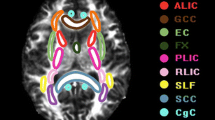

The diffusion images were first transformed to NII file format by using the dcm2nii tool, then, supplied to the diffusional kurtosis estimator (DKE) to generate DKI parameter maps. The T1WI acquired by MPRAGE were supplied to the SPM12 toolbox [29]. The DWI images (b = 0 s/mm2) were strictly aligned with T1WI space, and the transformed matrix was applied to the DKI parameter map. The DKI parameters of ROIs were automatically extracted by using MATLAB (2017a, The MathWorks, Inc., Natick, MA). The parameters of DKI include: MD, AD, RD, FA, MK, AK, RK, and KFA. MK, the most commonly used DKI parameter, means the average of the diffusion kurtosis along all diffusion directions; AK is the kurtosis along the axial direction of the diffusion ellipsoid; RK is the kurtosis along the radial direction of the diffusion ellipsoid; and FA is the most commonly used DTI parameter, which has been a primary imaging metric used in the evaluation of a wide range of neuropathologic processes [30]. The cingulum (CG) in the cingulate gyrus and the hippocampal regions is separated at the axial level of the splenium of the corpus callosum and denoted as CgC and CgH, respectively. CgC and CgH were selected as ROIs according to the ICBM template (see Fig. 2) [31].